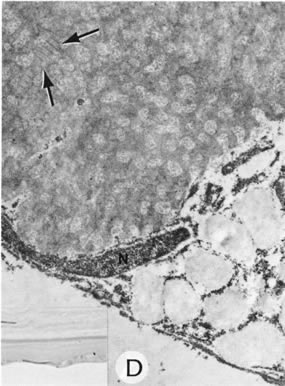

By light microscopy, eosinophilic intranuclear inclusions are characteristic of herpes simplex viral infections and represent the result of viral replication (Cowdri type A inclusions).121 Hypersensitivity type IV reactions in the stroma are characterized by lymphocytic and plasmacytic infiltrates. Intranuclear inclusions are relatively rare and are not found in most specimens. Viral particles occasionally can be found in multinucleated giant cells or within the stroma, especially in keratocytes (Figs. 20 and 21).

Fig. 20. Herpes simplex. A. Typical dendritic ulcer. B. Scanning electron micrograph of a dendritic ulcer in the epithelium of a rabbit cornea. C. Many intranuclear inclusions (arrows) are present in the corneal epithelium near the edge of the ulcer. D. Virus particles (arrows) of herpes simplex are present in the nucleus. E. Virus particles also are present within the cytoplasm. Note the large size of the cytoplasmic virions. Some particles show empty capsids, whereas others are complete, containing nucleoids. (Courtesy of SEI Photoarchives.) (B Courtesy of Dr. R. C. Eagle Jr; C from Font RL: Chronic ulcerative keratitis caused by herpes simplex virus. Arch Ophthalmol 90:382, 1973.)